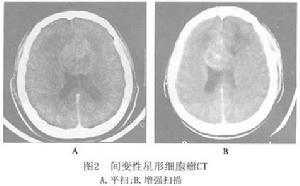

3.CT檢查 纖維型和原漿型星形細胞瘤,因組織含水量達81%~82%,CT多呈低密度,較均勻一致,占位效應不明顯 瘤內無出血灶或壞死灶,瘤周無明顯水腫影。除少數病例外,一般注射造影劑不增強或稍有增強。因腫瘤所在的部位和大小而異,表現相應的占位效應。小腦星形細胞瘤在CT上腫瘤的實質部分呈低(或)混雜密度病灶,造影劑增強後可有輕度增強,而囊腔部分則始終保持低密度影。囊壁部分可呈環形或弧線形增強。腦幹部位的星形細胞瘤CT上可見腦幹的增粗,左右不對稱及出現低密度或混雜密度的腫瘤病灶影, CT顯示腦幹膠質瘤不如MRI理想。部分腫瘤CT上呈等密度,從而使腫瘤在CT上難以發現,此時MRI可明確顯示腫瘤影(圖1)。

4.MRI檢查 星形細胞瘤在MRI上T1W呈低信號 T2W呈高信號。MRI可清楚顯示腫瘤浸潤腦組織的程度。增強後星形細胞瘤一般不強化, 少數腫瘤有周邊斑點狀輕度強化影。良性星形細胞瘤由於腫瘤的生長,使腫瘤內外水分增多,造成T1和T2延長 表現T1加權像呈低信號,T2加權像呈高信號(圖3),信號強度均勻,瘤周水腫輕微,注射Gd-DTPA增強不明顯。隨著腫瘤的生長,瘤內發生囊變使得MRI不均勻,瘤體和周圍水腫在T1加權像上不如T2加權像上容易區分,腫瘤可有輕度的增強, 惡性星形細胞瘤在T1加權相上呈混雜信號 以低信號為主,間以更低信號或高信號,體現了腫瘤內壞死或出血。